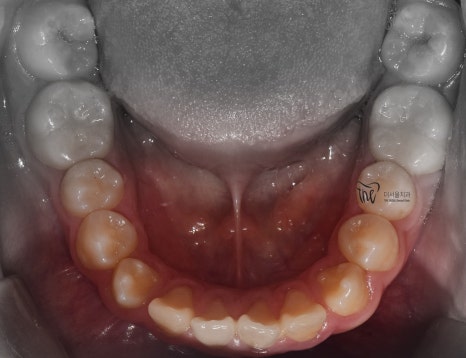

근데 또 교합면에서 보면, 악궁의 형태 자체는

그렇게 나쁜 편은 아닙니다. 다만, 회전이 되어있는

일부 치아들 및 치간이개의 현상 이외에는

별다른 특이사항을 볼 수 없죠.

교합면에서 봤을 때는, 거의 무턱 교정 치료가

다 끝난거와 같은 느낌을 받으실 수 있습니다.

원래, 악궁 자체는 그렇게 나쁜 편은

아니였기 때문에 크게 달라졌다고 느낌을

받기는 쉽지 않네요.